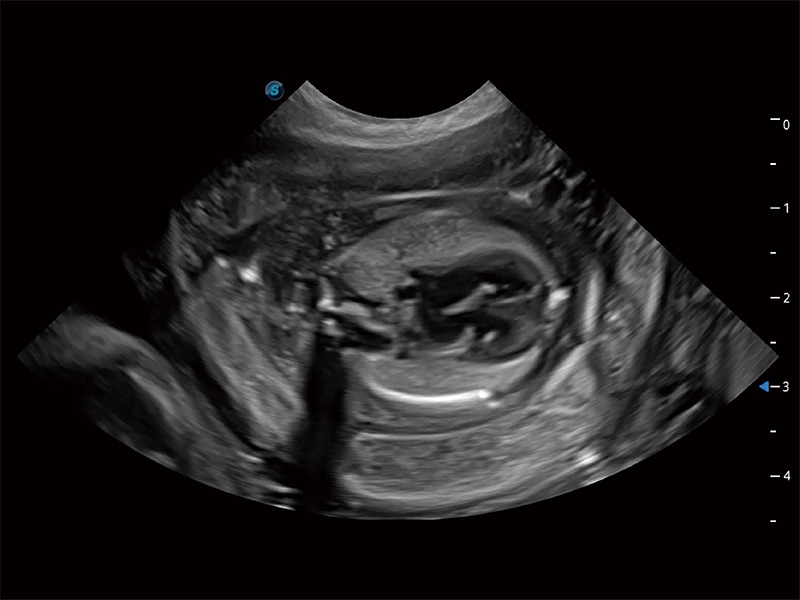

动物是人类最亲密的朋友和最值得信赖的伙伴。DB中国旗舰官方网站也一直致力于探索动物专用的超声影像解决方案。全新推出的ProPet系列,是DB中国旗舰官方网站在动物超声影像智能化、专业化、精准化的一次跨越式革新。动物不能用言语来表述自己的不适,通过超声影像,ProPet系列搭建了动物医生与不同物种沟通的“桥梁”,为动物医生注入了“治愈之力”。 ProPet 80 是DB中国旗舰官方网站匠心打造的一款高端动物专用彩超,采用性能卓越的全新硬件架构,极大提升超声系统的运行效率和数据处理能力,帮助动物医生从容应对日益增多的挑战性病例和日益多样化的临床需求。

ProPet 80 专为动物医生设计,对不同的动物体型和生理结构作出了针对性的优化。通过动物影像专用软件,可满足个性化的应用需求,帮助动物医生获得更精确的诊断数据。

ProPet 80 全新的动物超声智能软件和丰富的探头群,为动物医生提供了高清晰度和精细分辨率的图像,无论在宠物、马科、畜牧还是实验室动物等应用中都可以轻松应对,为您的日常工作带来满意的体验。